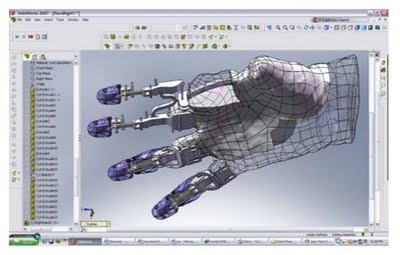

Fingers Restored By 3D Scanning

Did you ever take a very close look at your fingers? They are incredibly complex machines, with not only shape and texture, but also motion. Imagine if fate caused the loss of one or more of them? There are solutions today, such as those produced by Didrick Medical, who make a kind of finger-harness that… Continue reading Fingers Restored By 3D Scanning